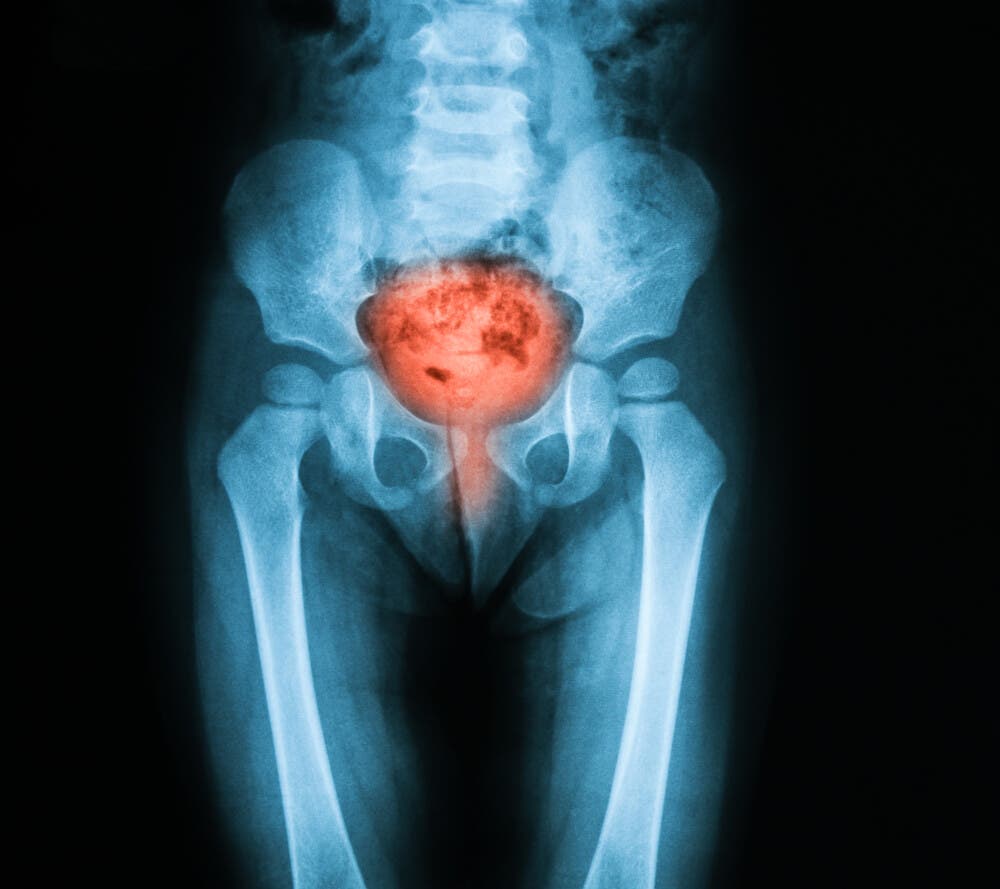

La vejiga es un órgano muscular hueco y allí se deposita la orina. Se expande para almacenarla y se relaja para expulsarla. Con la cistometría se obtiene información sobre la forma como se lleva a cabo ese proceso.

En términos generales, la cistometría permite establecer si hay incontinencia urinaria o retención de la orina. Hay afecciones de la misma vejiga, de la uretra o de otro tipo que pueden causar estas anomalías.

Una cistometría se emplea para establecer si la vejiga funciona bien y, en caso de no hacerlo, el examen brinda información para determinar la posible causa. Es necesaria si hay sospecha de algunas afecciones como las siguientes:

- Problemas de la vejiga. Incluye la capacidad de vejiga reducida, la vejiga hiperactiva, el vaciado incompleto, etc.

- Disfunción neurógena de la vejiga. Ocurre cuando la vejiga funciona mal por efecto de un problema en el sistema nervioso, como un tumor de médula, por ejemplo.

- Lesión de la médula espinal. Las señales de la vejiga se envían al cerebro a través de la médula espinal. Si esta tiene una lesión, afecta la función de la vejiga.